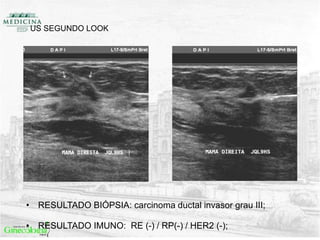

US SEGUNDO LOOK

• RESULTADO BIÓPSIA: carcinoma ductal invasor grau III;

• RESULTADO IMUNO: RE (-) / RP(-) / HER2 (-);